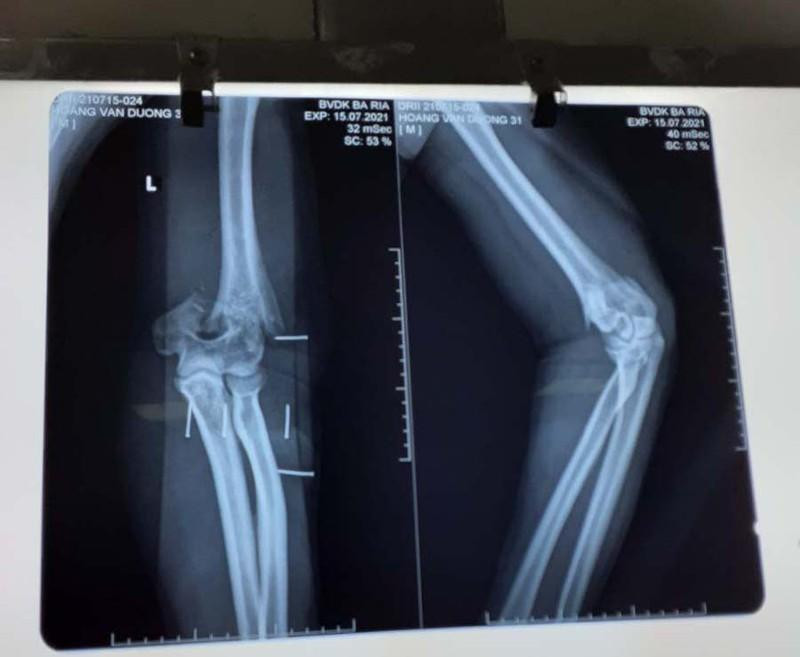

| Hình chụp phim thương tích ở cánh tay của thượng úy Hoàng Văn Dương. Ảnh: BV. |

Trong khi đó, bác sĩ CKI Lại Thế Sở, khoa Ngoại Chấn thương Chỉnh hình, Bệnh viện Bà Rịa, tỉnh Bà Rịa-Vũng Tàu cho biết, bác sĩ tiến hành phẫu thuật cho thượng úy Dương. Tình trạng vết thương của bệnh nhân trước khi mổ là bị cắt đứt phần gân cơ, phần mềm phía sau khuỷu tay, chém gãy lìa đầu dưới xương cánh tay.

Các bác sĩ đã phẫu thuật kết hợp xương và khâu nối các cấu trúc bị tổn thương. Sau khi mổ gắn lại xương. Ca mổ tiến hành trong 3h. Hiện tại, sức khỏe của thượng úy Dương ổn định, chờ thời gian phục hồi các tổn thương. Sau này khả năng phục hồi vận động tốt.